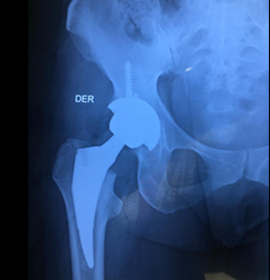

La artroplastia de reemplazo, o cirugía de reemplazo articular , es un procedimiento quirúrgico el cual consiste en sustituir una superficie articular artrítica o disfuncional por edad o por enfermedades que afectan a dicha articulación por una prótesis ortopédica.

El reemplazo articular se considera una opción cuando el dolor o la disfunción de la articulación es severo brindándole al paciente una nueva oportunidad de calidad de vida.

Procedimiento quirúrgico el cual consiste en sustituir una superficie articular artrítica o disfuncional por edad o por enfermedades que afectan a dicha articulación por una prótesis ortopédica.

Egresado de la UNAM, y certificado por el consejo mexicano de ortopedia, quien brinda atención en padecimientos musculoesqueléticos, experto en problemas articulares avanzados, cirugías por artroscopia y colocacion de protesis de cadera y rodilla.